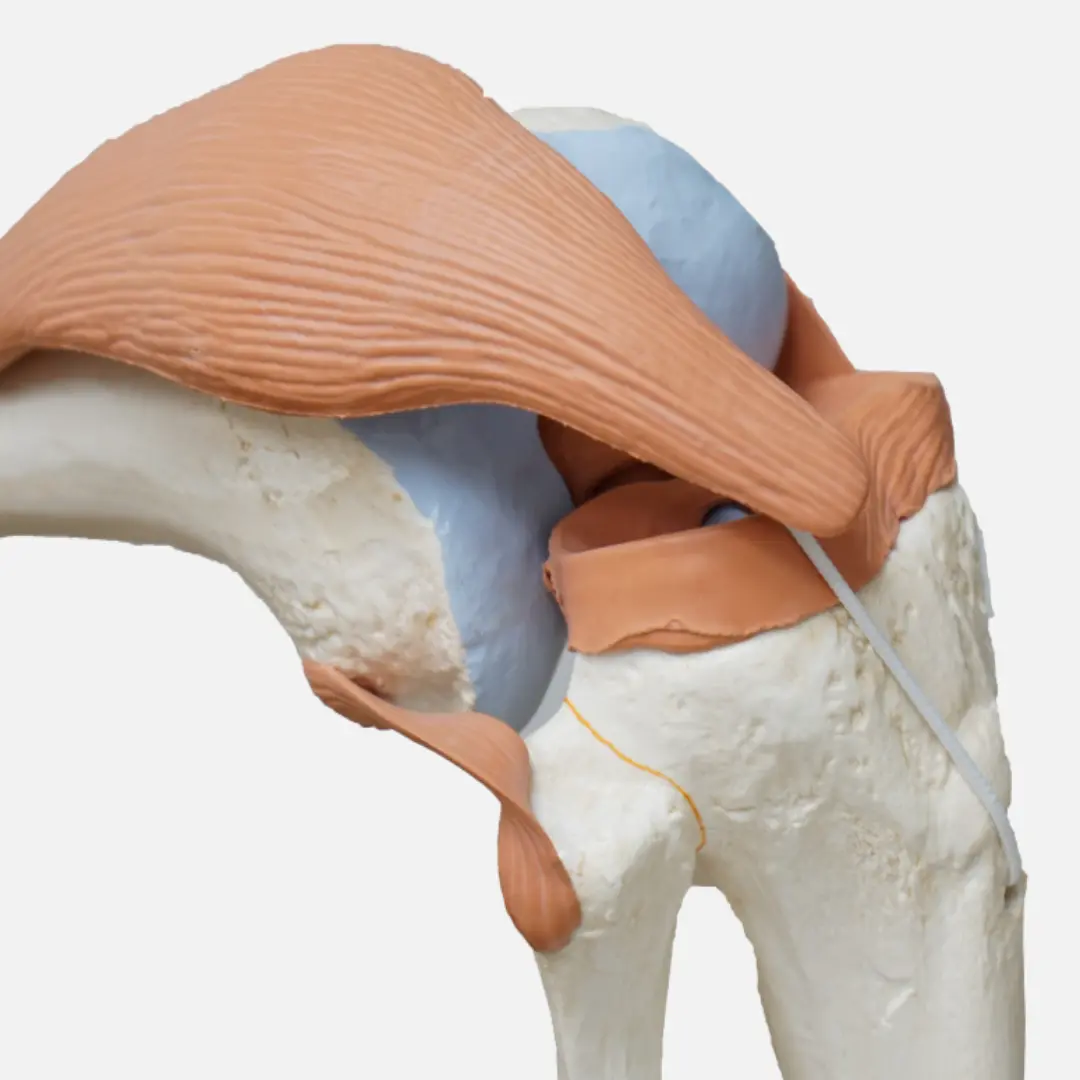

십자인대 파열은 무릎 관절 내에 위치한 중요한 인대인 전방 십자인대(ACL) 또는 후방 십자인대(PCL)가 손상되어 발생하는 부상이에요. 주로 스포츠 활동 중 갑작스러운 방향 전환, 급격한 감속, 무릎에 가해지는 직접적인 충격 등으로 인해 발생하며, 파열 정도에 따라 증상이 다르게 나타날 수 있어요.

전방 십자인대 파열 시에는 '뚝'하는 파열음과 함께 심한 통증이 즉시 발생하고, 무릎이 불안정하게 흔들리는 느낌을 받을 수 있어요. 부상 직후에는 무릎이 붓고 움직이기 어려워지며, 시간이 지나면서 통증은 감소하지만 무릎의 불안정감은 지속될 수 있어요.

후방 십자인대 파열은 전방 십자인대 파열보다 발생 빈도는 낮지만, 무릎 앞쪽으로의 직접적인 충격이나 과도한 꺾임 등으로 인해 발생할 수 있으며, 통증과 함께 무릎 뒤쪽의 뻐근함, 무릎을 굽히거나 계단을 내려갈 때 불편함이 나타날 수 있어요.

완전 파열의 경우에는 수술적 치료가 일반적으로 권장되며, 주로 관절 내시경을 이용하여 자가 건이나 동종 건을 이식하는 십자인대 재건술을 시행해요. 수술 후에는 체계적인 재활 치료가 매우 중요하며, 이는 통증 및 부종 관리, 관절 운동 범위 회복, 근력 강화, 균형 감각 훈련 등을 포함하여 수개월에 걸쳐 진행돼요.